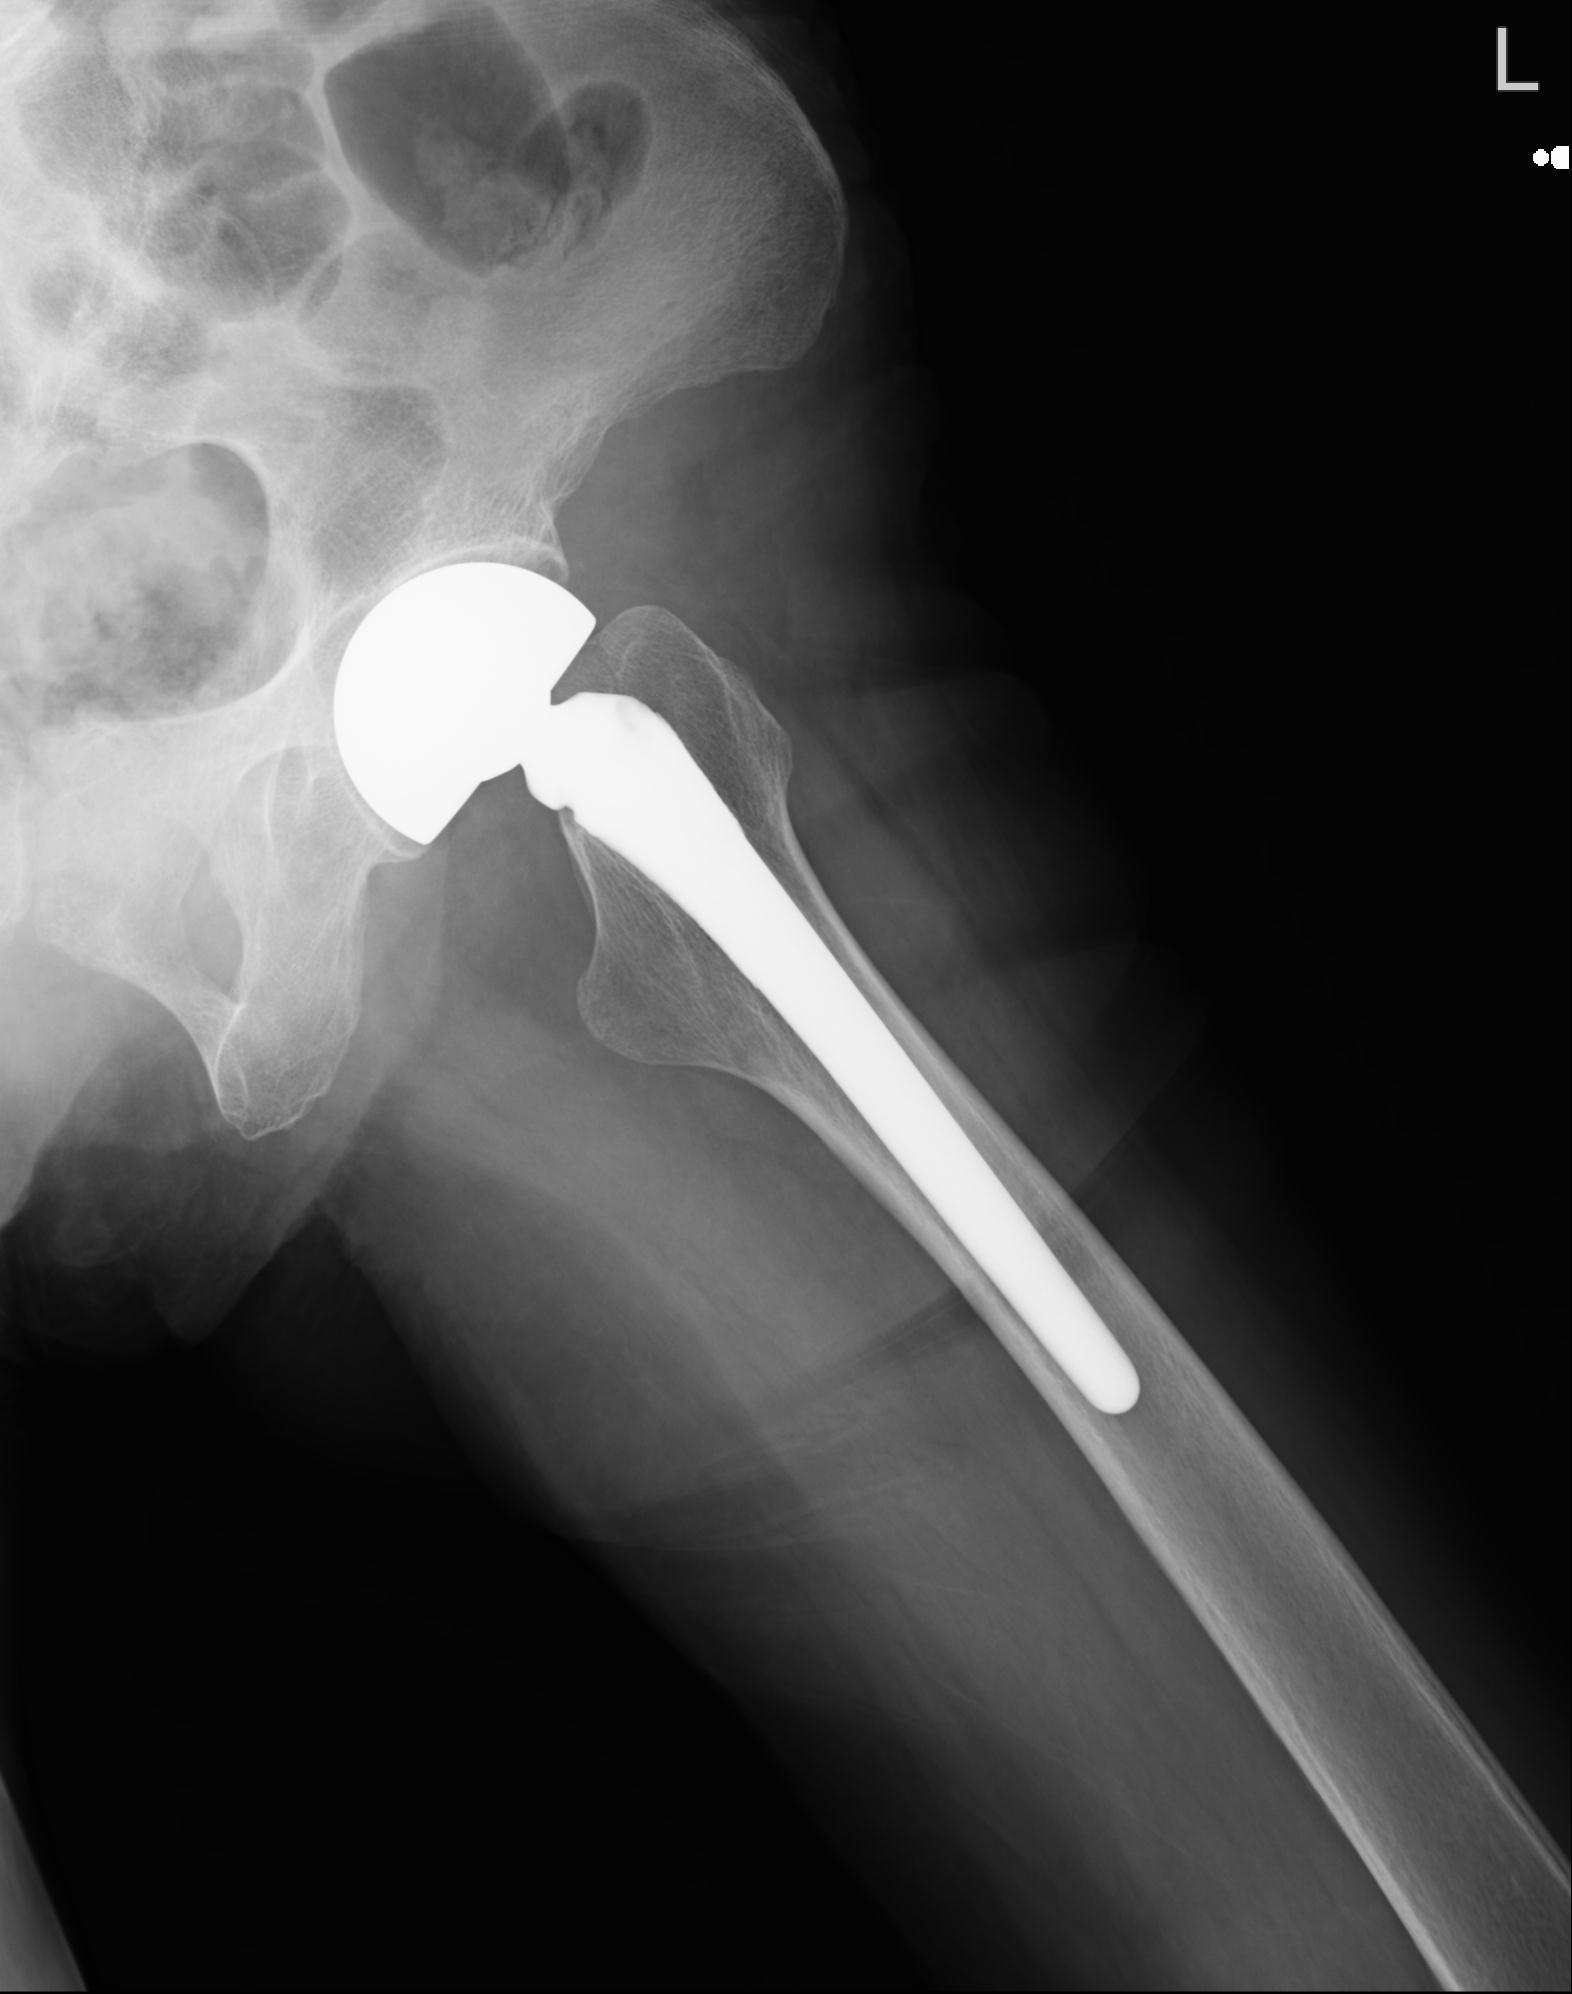

110286 2/17 股関節 2R 74歳女性 右人工骨頭

82084 1/14 1/20 股関節 2R 78歳男性 右人工骨頭